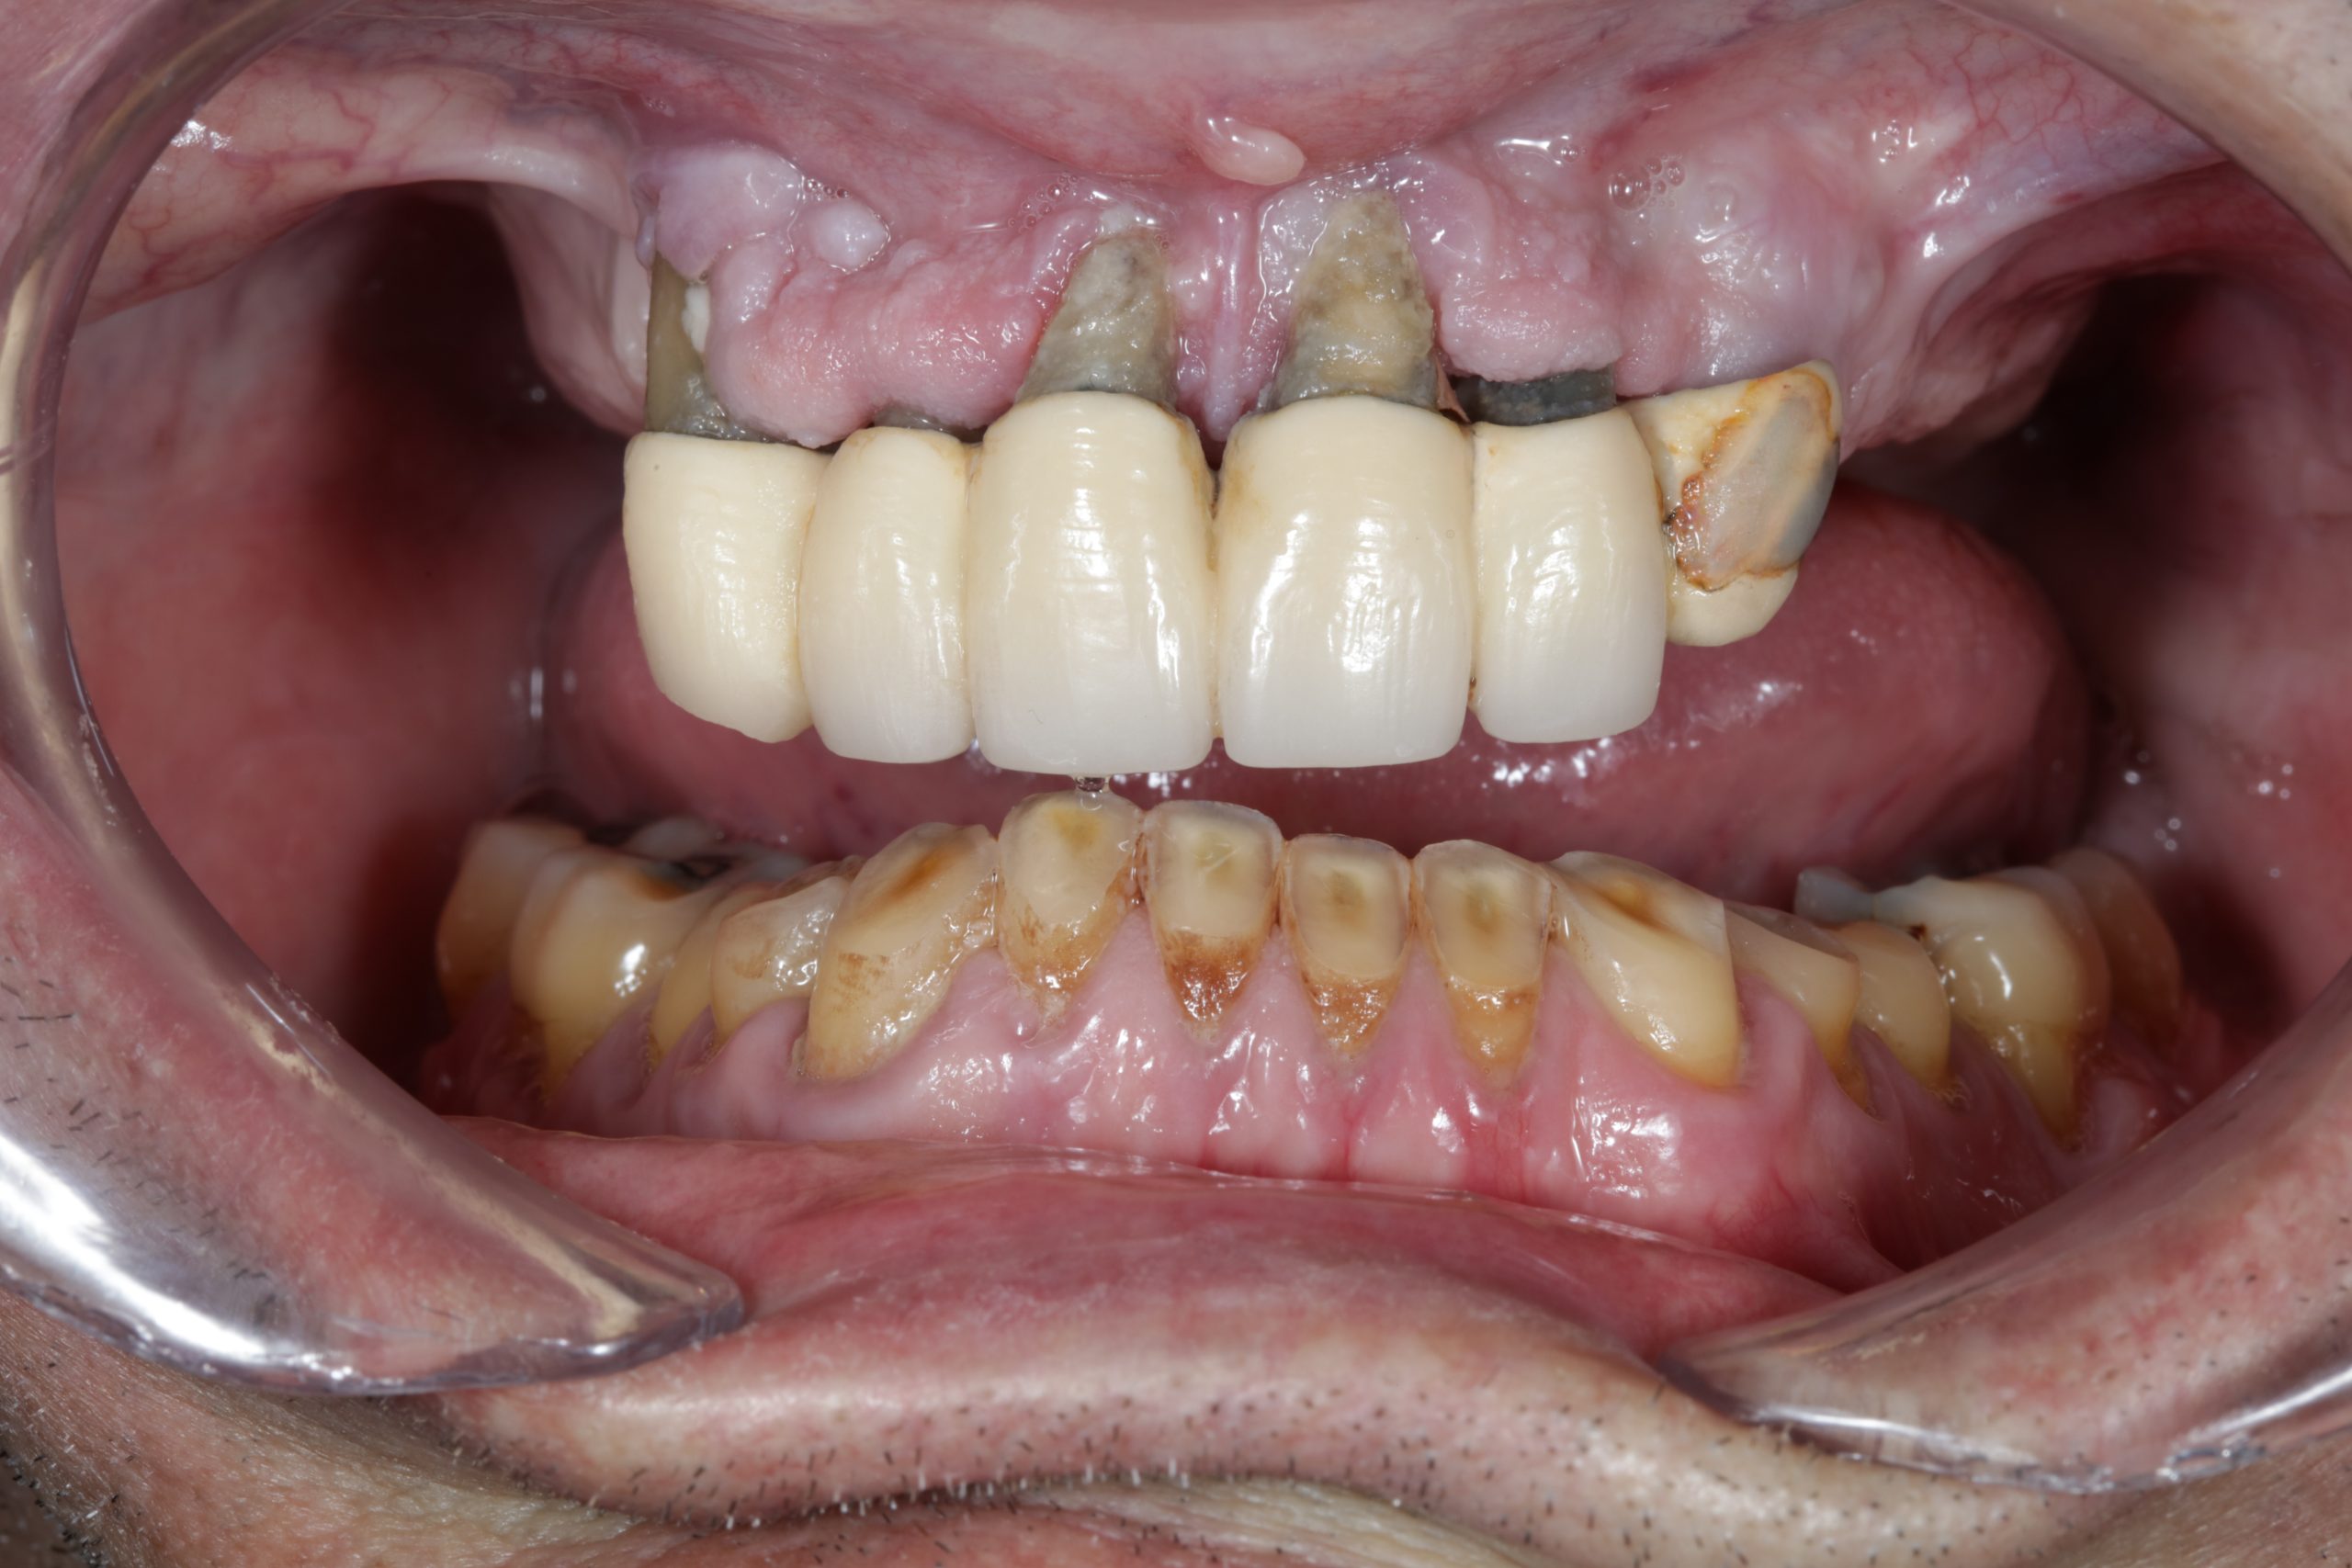

Implants & Crowns

Prosthetics from traditional impressions and digital files on preparations and implants.